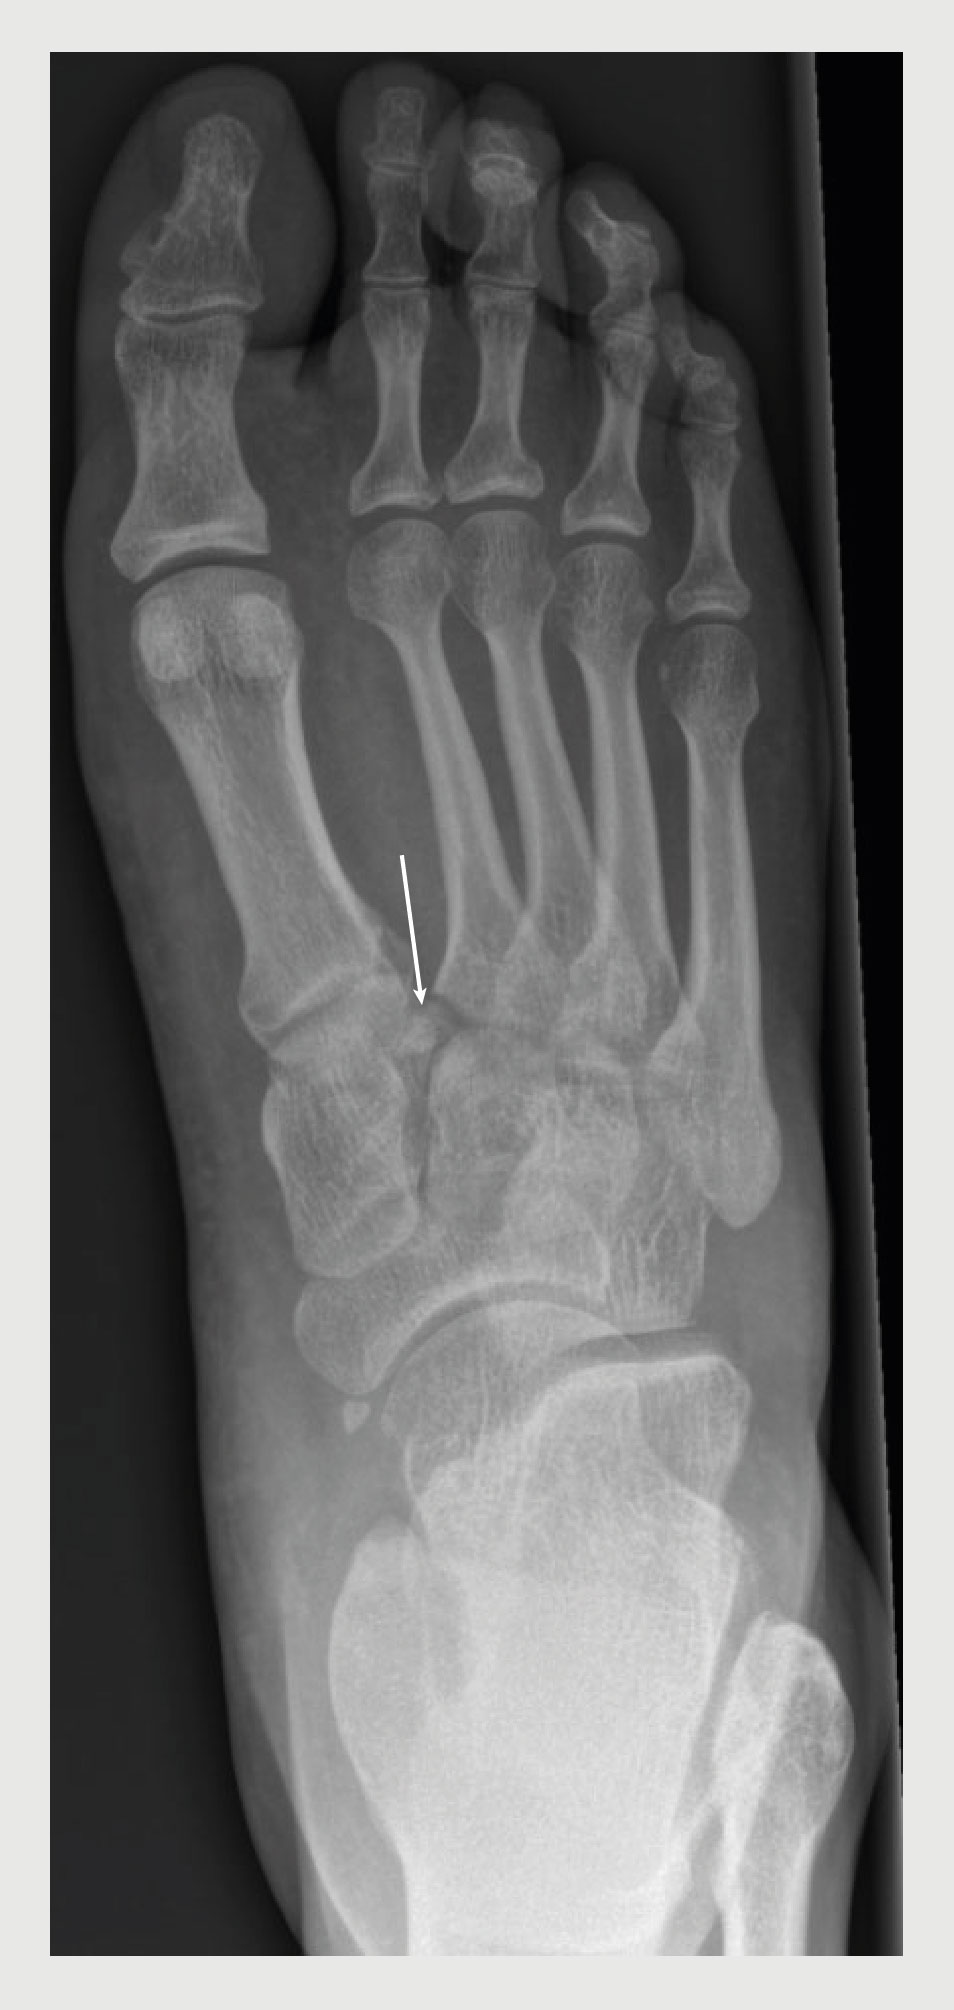

In de twee weken daarna hielden de klachten aan. Doordat de eigen huisarts afwezig was, werd de patiënt een week later pas verwezen naar de polikliniek Heelkunde. Aldaar zagen wij een patiënt met zwelling van de rechter voet, meest uitgesproken op de middenvoet. Tevens was er sprake van een plantair hematoom. Dwarse compressie van de metatarsofalangeale (MTP-)gewrichten en passieve pronatie of abductie van de voorvoet veroorzaakte pijn in de middenvoet. Instabiliteit van de middenvoet konden we echter niet objectiveren. Vanwege de symptomen en het klinisch beeld stond een Lisfranc-letsel hoog in onze differentiaaldiagnose. De recente röntgenfoto’s van de rechter voet werden opnieuw beoordeeld, waarbij fractuurfragmenten werden gezien tussen het os cuneiforme mediale (C1) en de basis van os metatarsale (MT-)II (figuur 2). Er werd een aanvullende CT-scan van de rechter voet gepland. In afwachting van de CT-scan kreeg de patiënt een onderbeengips om de zwelling te verminderen.

Figuur 2 | Röntgenfoto van voet van de patiënt

Anteroposterieure röntgenfoto van de rechter voet van een 51-jarige man met pijn en zwelling van de voet nadat hij was gestruikeld. Er zijn fractuurfragmenten zichtbaar tussen de basis van os metatarsale II en het os cuneiforme mediale, ook wel het teken van Fleck genoemd (‘Fleck sign’; zie pijl).

Hoewel fractuurdislocatie onmiskenbaar is op standaard röntgenfoto’s, is subtiel ossaal of ligamentair letsel vaak minder evident. Avulsiefragmenten van C1 of van de basis van MT-II, oftewel het ‘Fleck sign’, en diastase tussen de basis van MT-I en -II, ook wel ‘gap sign’ genoemd, zijn pathognomonisch voor een Lisfranc-letsel. Wees verder bedacht op een Lisfranc-letsel wanneer er sprake is van ander ossaal letsel rond het tarsometatarsale gewricht.